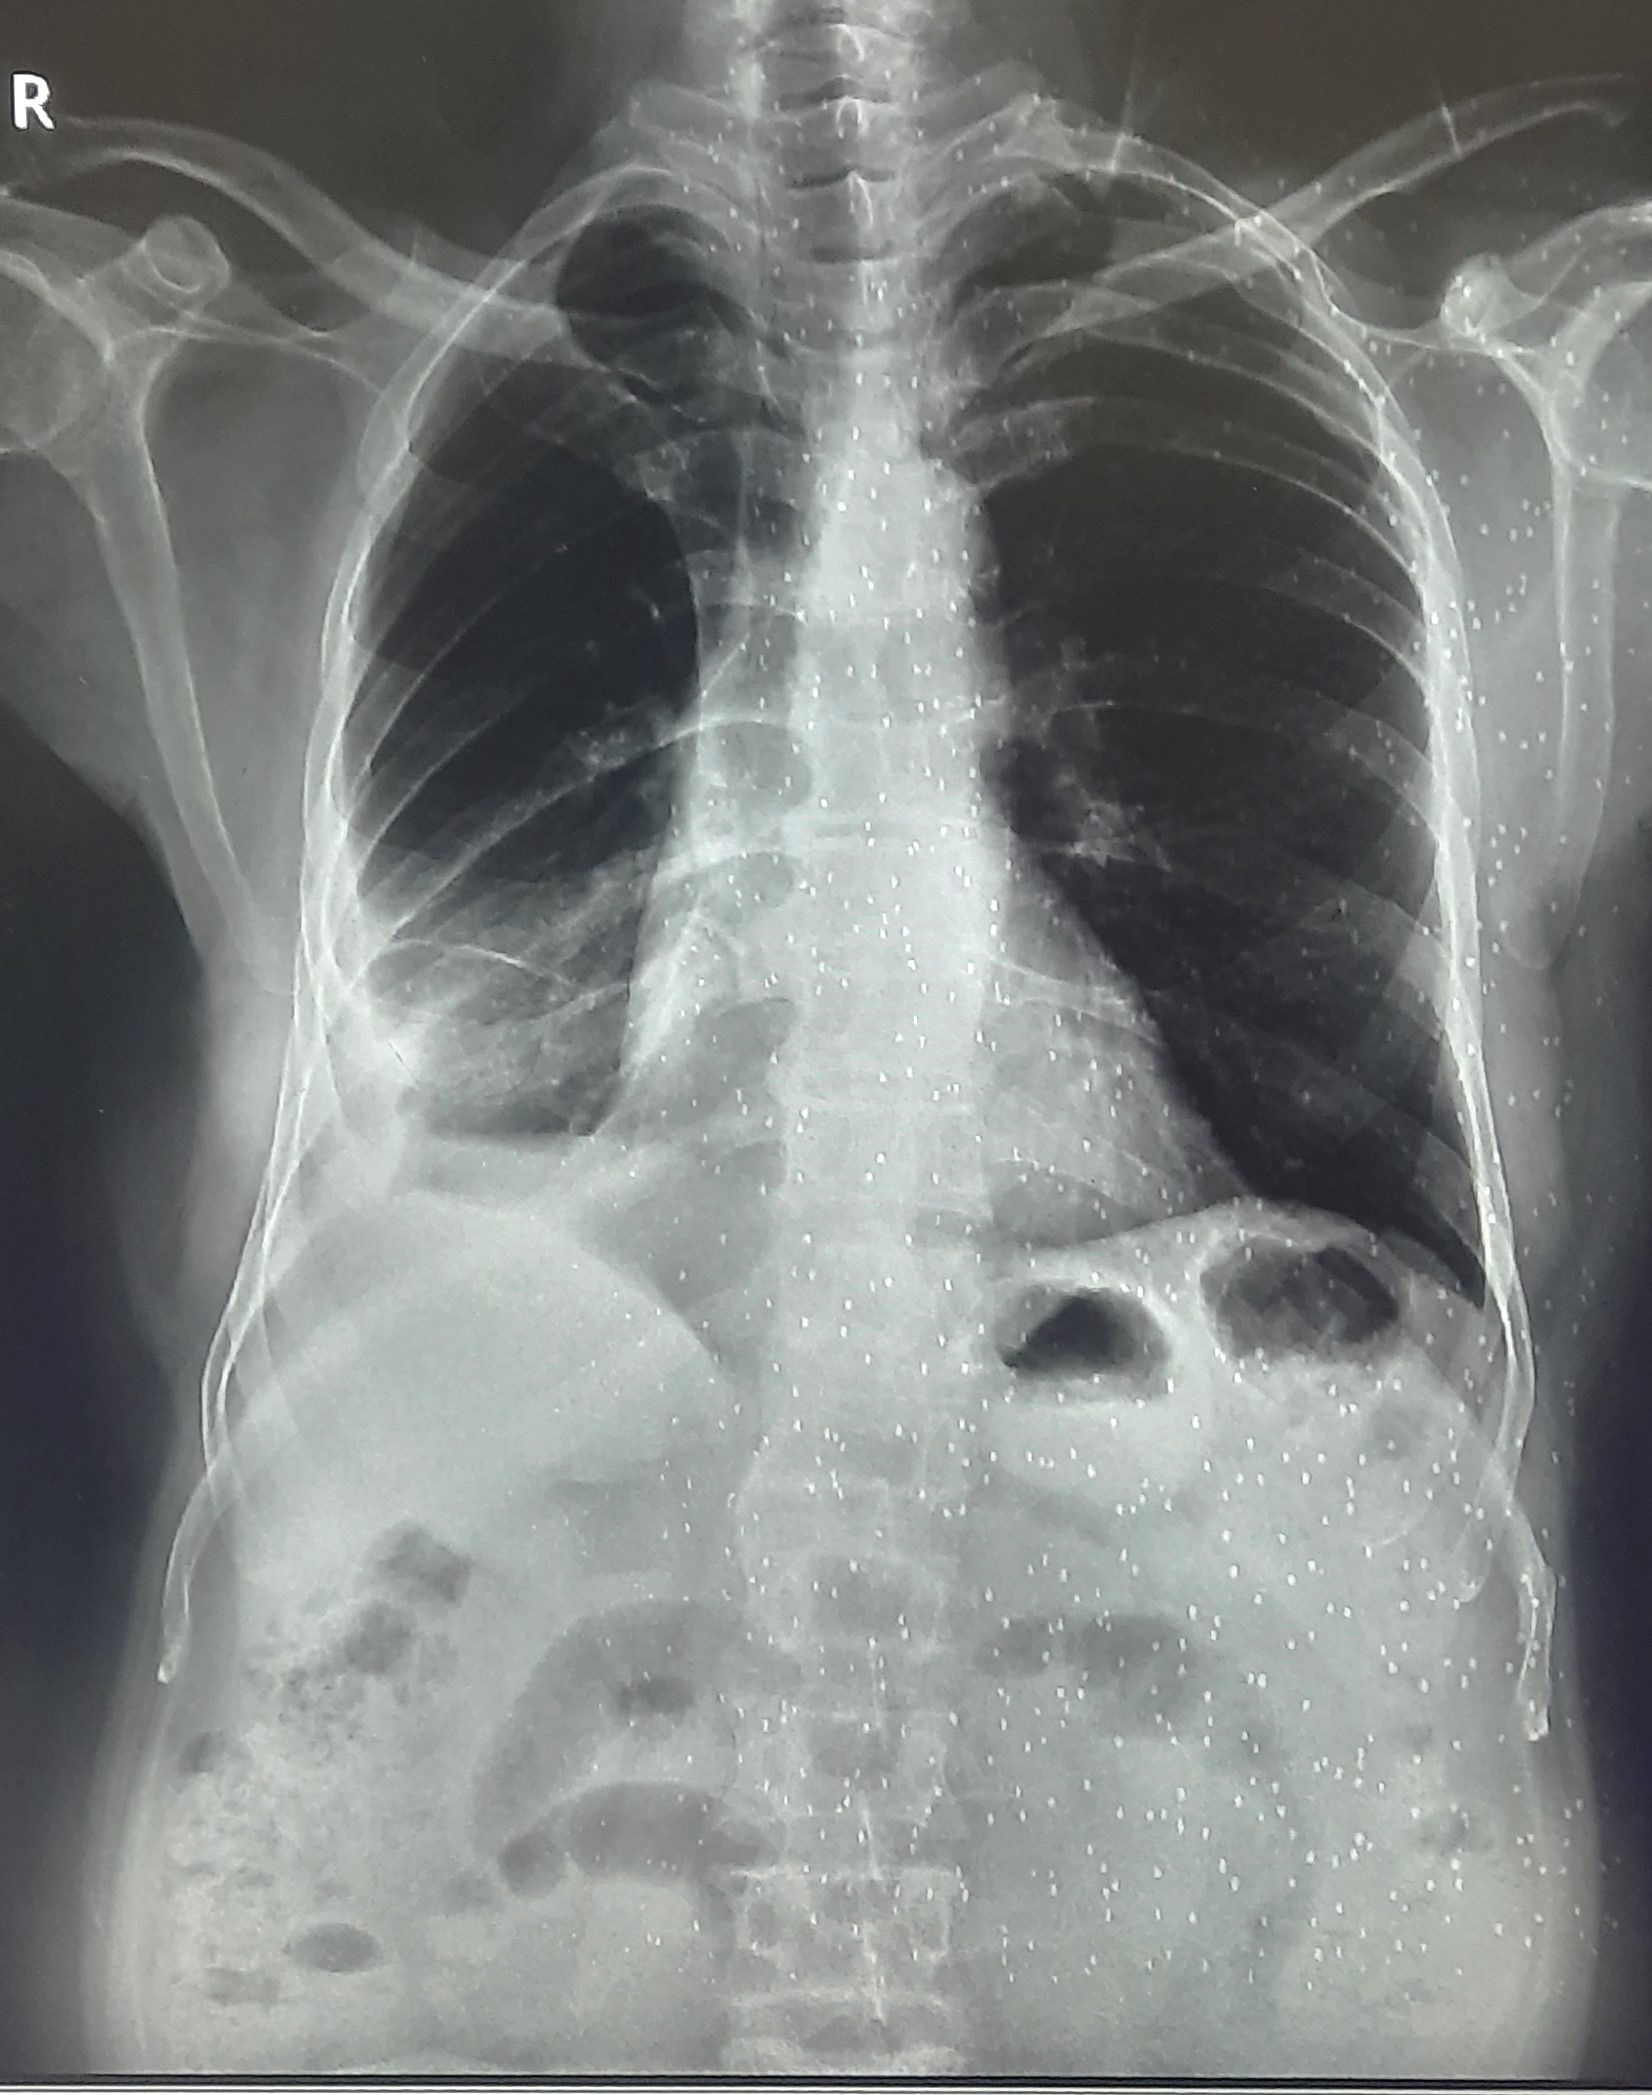

| 205 | IGGMC, Nagpur, Nagpur | P2 | 29-4267 | MOHAMMAD HANIF SUREYYA | Consent taken on Paper | 55 Yrs. |

Provisional Diag : PTB?

Final Diag : PNAEMOTHORAX /CLINICALLY DIAGNOSED PTB |

TB Case (Confirmed) | LEFT SIDED PNAEMOTHORAX | Abnormality visible on x-ray |

View |